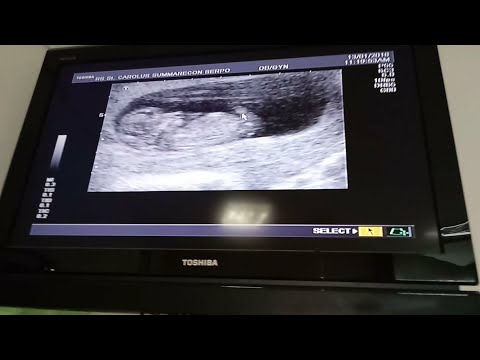

Video: Pemeriksaan USG , RS ST. Carolus hospital serpong summarecon